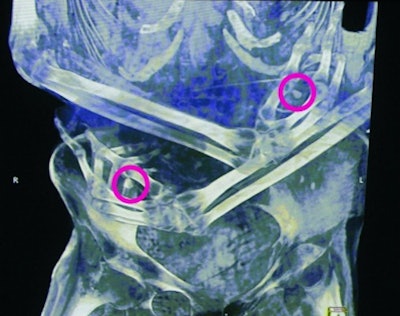

Dental condition and various skeletal characteristics were used to determine the age of this woman, with artificial cranial deformity, at between 20 and 40 years of age. Her left collarbone was fractured and poorly consolidated. Some thoracic and lumbar vertebrae show signs of tuberculosis. Calcifications in the lung tissue are also indicative of this infectious disease. CT scan also revealed two objects, approximately 1 cm in size, placed in her hands. The size and shape of the 3D printed replicas reveal that they are human milk teeth. The reason for their presence is unknown.